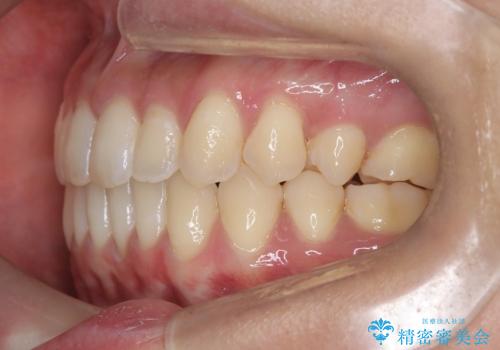

再矯正 前歯のガタツキをマウスピース矯正で治療したい

- 前に矯正治療をしたが、後戻りしてガタツキが出てきたので、治したいとのことで来院されました。

ワイヤー治療とマウスピース矯正、2通りの治療を提案させていただき、マウスピース矯正治療を希望されましたので、インビザラインによる治療を開始しました。